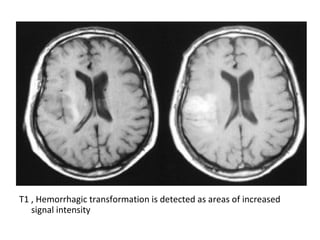

9-Hemorrhage :

-Hemorrhagic transformation is a little variably

used and collectively refers to two different

processes which have different incidence ,

appearance and prognostic implications ,

these are :

T1 , Hemorrhagic transformation is detected as areas of increased

signal intensity , the gyral pattern of increased signal intensity may

also represent cortical laminar necrosis

signal intensity